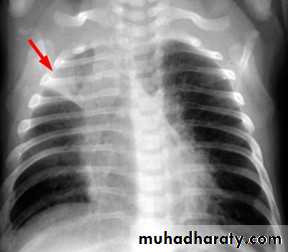

Right upper lobe consolidation

RUL consolidation will be seen as an increased opacity within the right upper lobe. Opacity may be sharply bordered by the horizontal fissureSome loss of outline of the upper right heart border may be apparent

Radiological sign in chest radiograph

Dense opacity seen above the horizontal fissure.

Air-bronchogram line

The lower border of the consolidation is sharply delinated by the horizontal fissure suggesting it lies in the anterior segment of the RUL